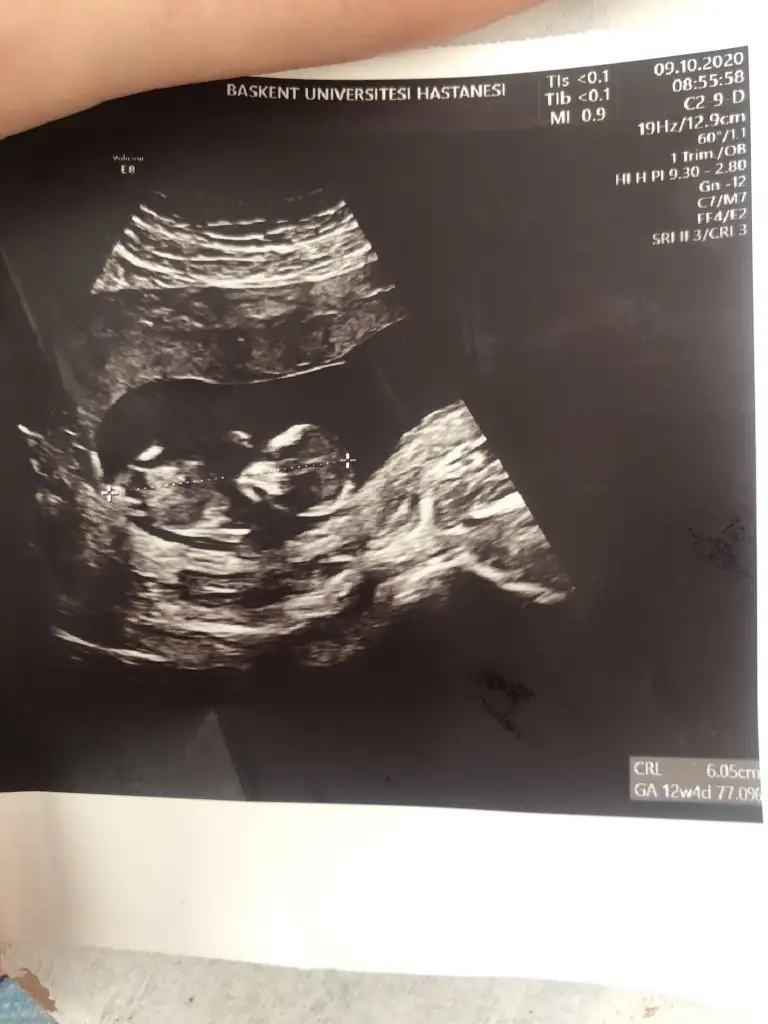

Günaydın kızlar doktordan geldim ikili test vardı kan verdim. Cinsiyeti söyleyecekti ben söylemeyin belliyse kağıda yazın dedim.yazacak kadar belli değil dedi burun kemiği görüldü ense kalınlığı da normal çok şükür darısı gidecek arkadaşlara🥰🥰

• 77534A5E-A69E-4B6A-B32B-25413C63432F.webp

77534A5E-A69E-4B6A-B32B-25413C63432F.webp

30,4 KB · Görüntüleme: 79